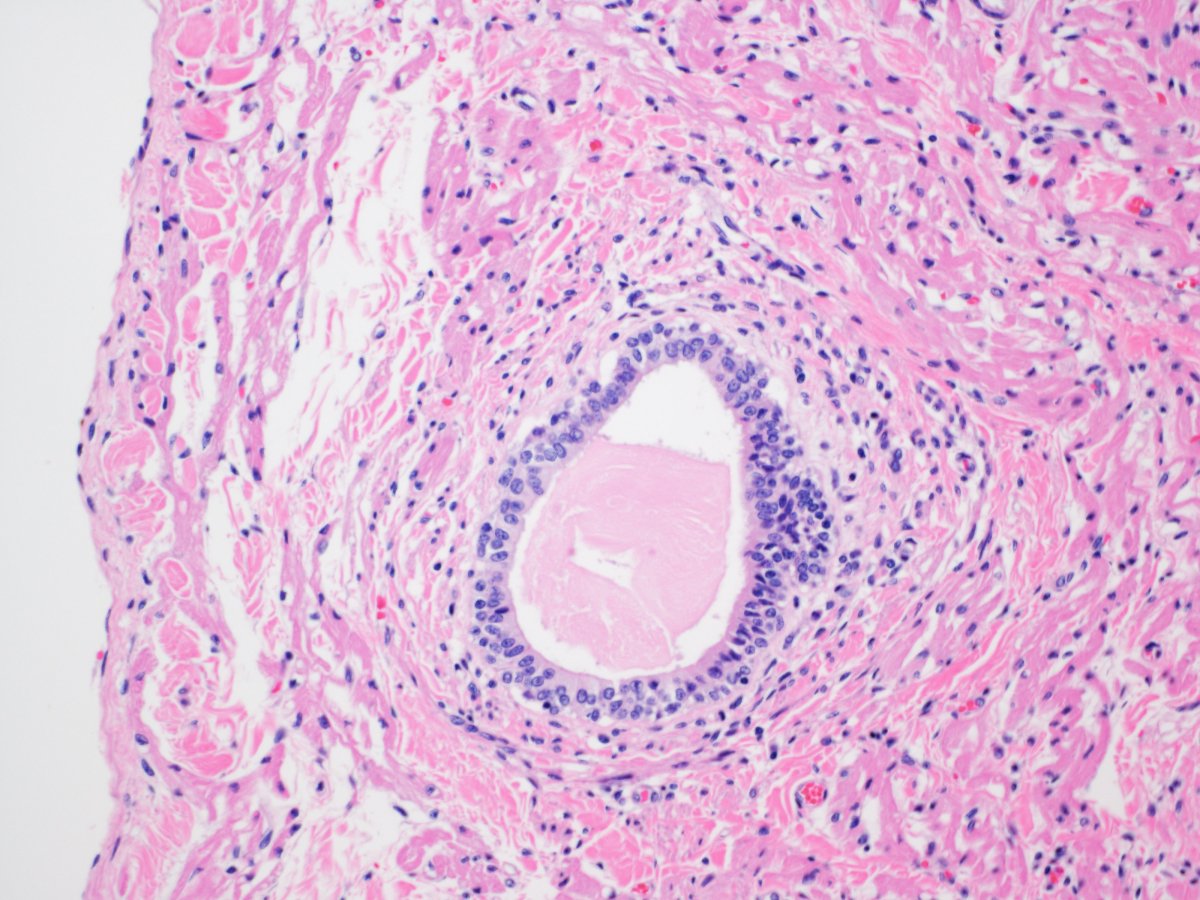

Incidental histological finding on the endocardium of the right ventricle in a 56-year-old male

#cardiacpath #CVPath #mumbaicvp @_SaranyaS_ @fabiotavora @kinasa85 @MelanieBoisMD @IvanaKholova @AECVPCam2021 @UKCardiacPath @CryCardiac @SCVP1 @kriyer68 @thejourneymate

Cellular Cardiac Myxoma: New histopathological subtype?

The tumor was more cellular with predominant trabecular pattern with few single cells and Vasoformative pattern. The extracellular myxoid matrix was less and shows tiny cystic vacuoles.